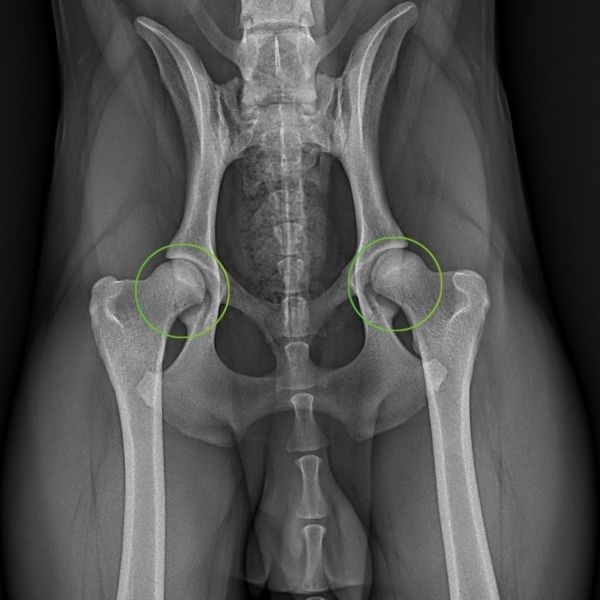

Zum Vergleich ein Röntgenbild einer gesunden Hüfte. Die Oberschenkelköpfe liegen in den Gelenkpfannen. Es ist keine Einschränkung erkennbar.